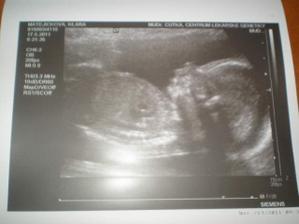

Baby č.2

dekuju tak v 5tt jeste srdicko neni ale jsem rada ze jsem tam kde mame byt a doufam ze pristi tyden bude srdicko